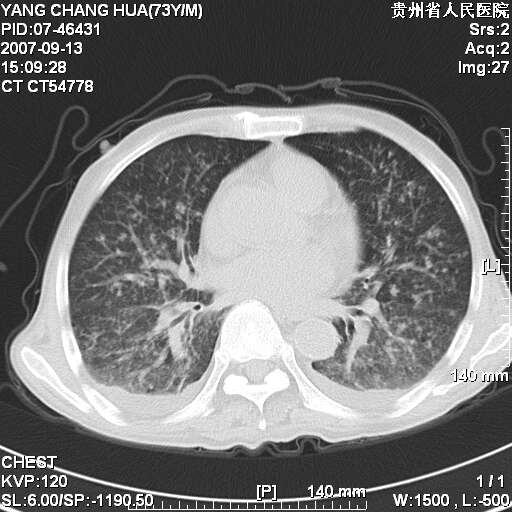

图像没有传全。肺部为感染性病灶;肺囊肿;双侧胸腔积液;肝脾肿大;腹水。

双肺部为感染性病灶.双侧胸腔积液;肝脾肿大;腹水.

双肺部为感染性病灶.双侧胸腔积液;肝脾肿大;脾脏密度不均,不除外脾侵润?腹水.

双肺点片状影,以双上肺改变明显.双侧胸腔积液.为感染性病灶,但不除外结核.

双上肺继发型肺结核。

肺大泡。

双肺散在斑片状及多发小结节状阴影,边缘模糊,双上肺野明显,双侧胸膜腔少量积液,纵隔及肺门区未见明显肿大淋巴结,肝脾肿大,脾内见多发低密度区,结合临床考虑恶性淋巴瘤(肺内表现为肺炎肺泡型),单看影像表现,肺结核不能排除。建议结合实验室检查或表浅淋巴结活检。